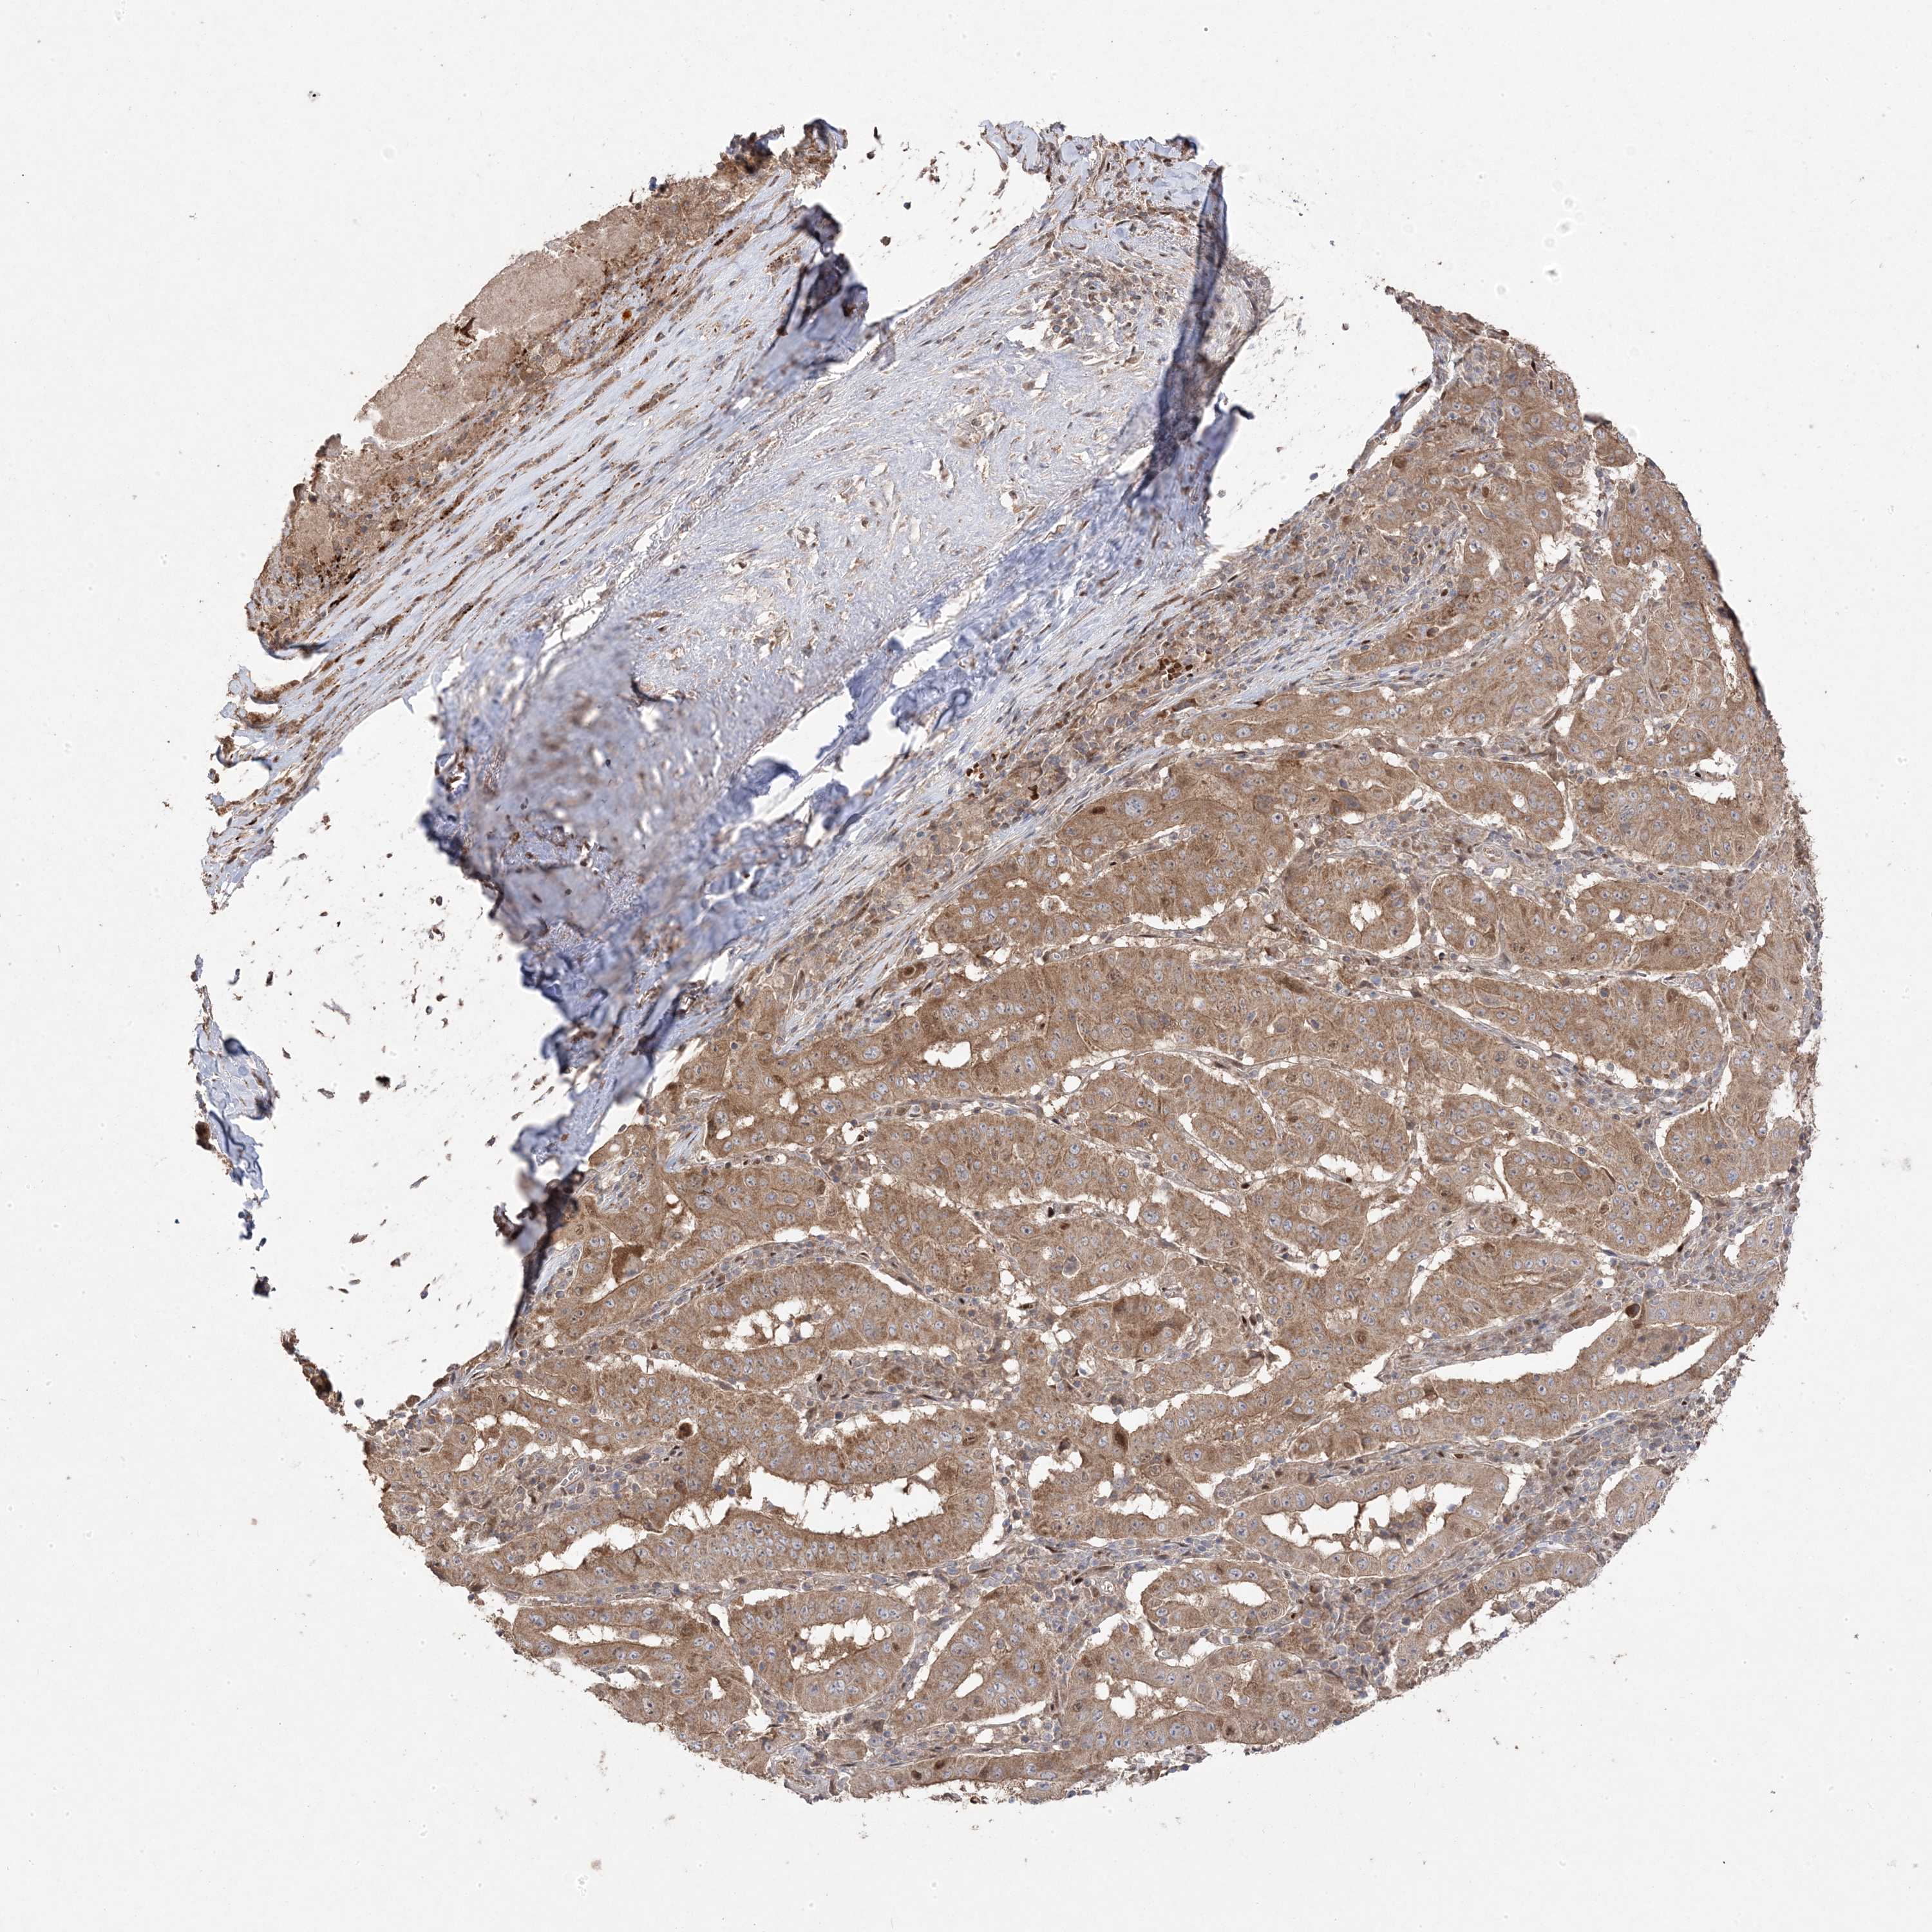

PANCREATIC CANCER - Protein expressioni

A mouse-over function shows sample information and annotation data. Click on an image to view it in a full screen mode. Samples can be filtered based on level of antibody staining by selecting one or several of the following categories: high, medium, low and not detected. The assay and annotation is described here.

Note that samples used for immunohistochemistry by the Human Protein Atlas do not correspond to samples in the TCGA dataset.

Antibody stainingi

Antibody staining in the annotated cell types in the current human tissue is reported as not detected, low, medium, or high, based on conventional immunohistochemistry profiling in selected tissues. This score is based on the combination of the staining intensity and fraction of stained cells.

Each image is clickable and will lead to virtual microscopy that enables deeper exploration of all samples and also displays staining intensity scores, fraction scores and subcellular localization as well as patient and tissue information for each sample.

Antibody HPA030123

Staining

High

Medium

Low

Not detected

Intensity

Strong

Moderate

Weak

Negative

Quantity

>75%

75%-25%

<25%

None

Location

Nuclear

Cytoplasmic/membranous

Cytoplasmic/membranous,nuclear

Adenocarcinoma, NOS